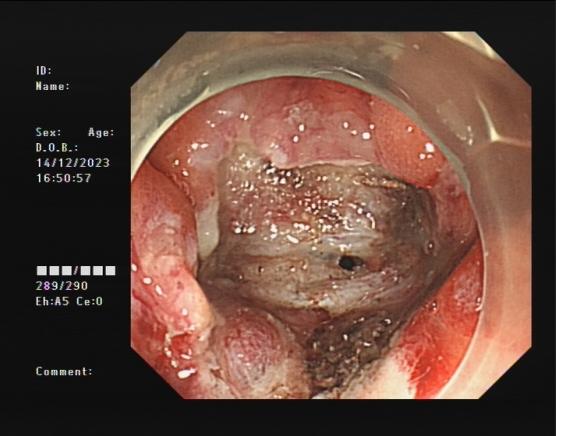

直腸側向發育性腫瘤      內鏡下黏膜下剝離術后創面

內鏡下黏膜剝離術(ESD):治療巨大平坦息肉,早期癌及癌前病變,黏膜下腫瘤等。